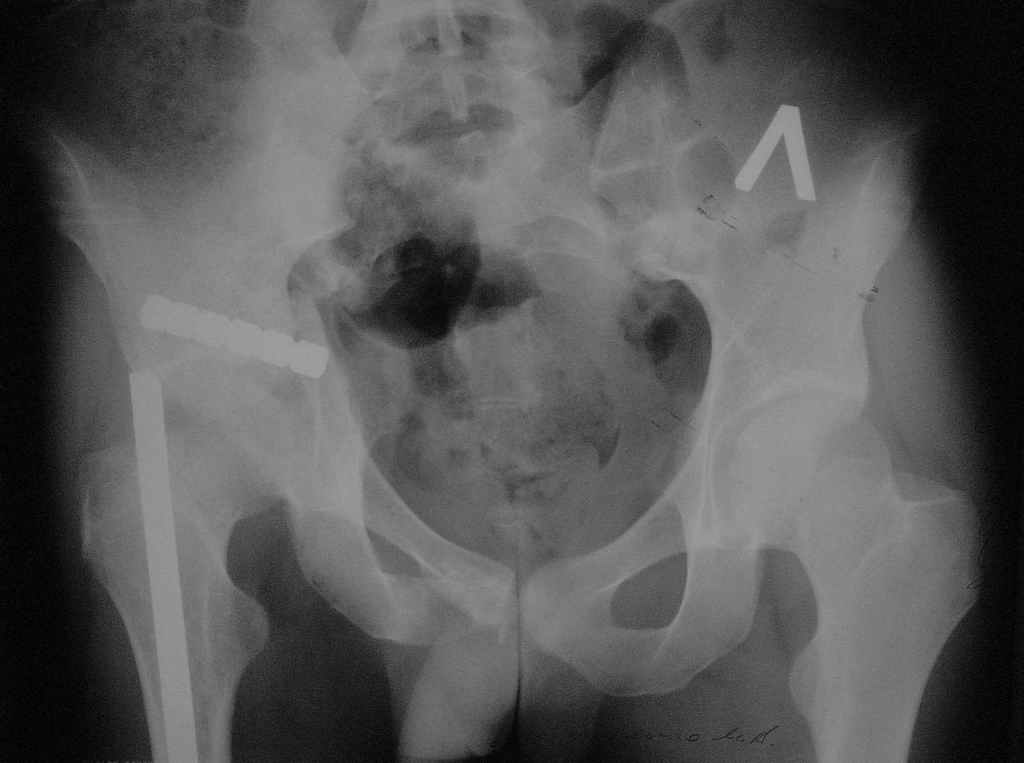

Больной Л. М. В., 23 лет, находился на лечении во Взрослом ортопедическом отделении № 2 Краевой больницы № 2 г.Хабаровска с 28 августа 2004 г. по 25 октября 2004 г. с диагнозом: Автотравма 25.07.04 г. Закрытый несвежий осложненный оскольчатый перелом задней колонны и крыши вертлужной впадины справа с задним подвывихом головки бедренной кости. Травматический неврит седалищного нерва справа на уровне тазобедренного сустава с выпадением функции (до пареза) малоберцовой порции. Закрытый вертикальный перелом боковых масс крестца справа со смещением правой половины таза кверху. Срастающийся перелом с/3 правой бедренной кости, фиксированный интрамедуллярно стержнем. Ранний восстановительный период ЗЧМТ.

01.09.04 г. Открытая репозиция перелома правой вертлужной впадины, невролиз седалищного нерва, накостный остеосинтез реконструктивной пластиной. Чрескостный остеосинтез костей таза спице-стержневым аппаратом внешней фиксации <таз-бедро>.